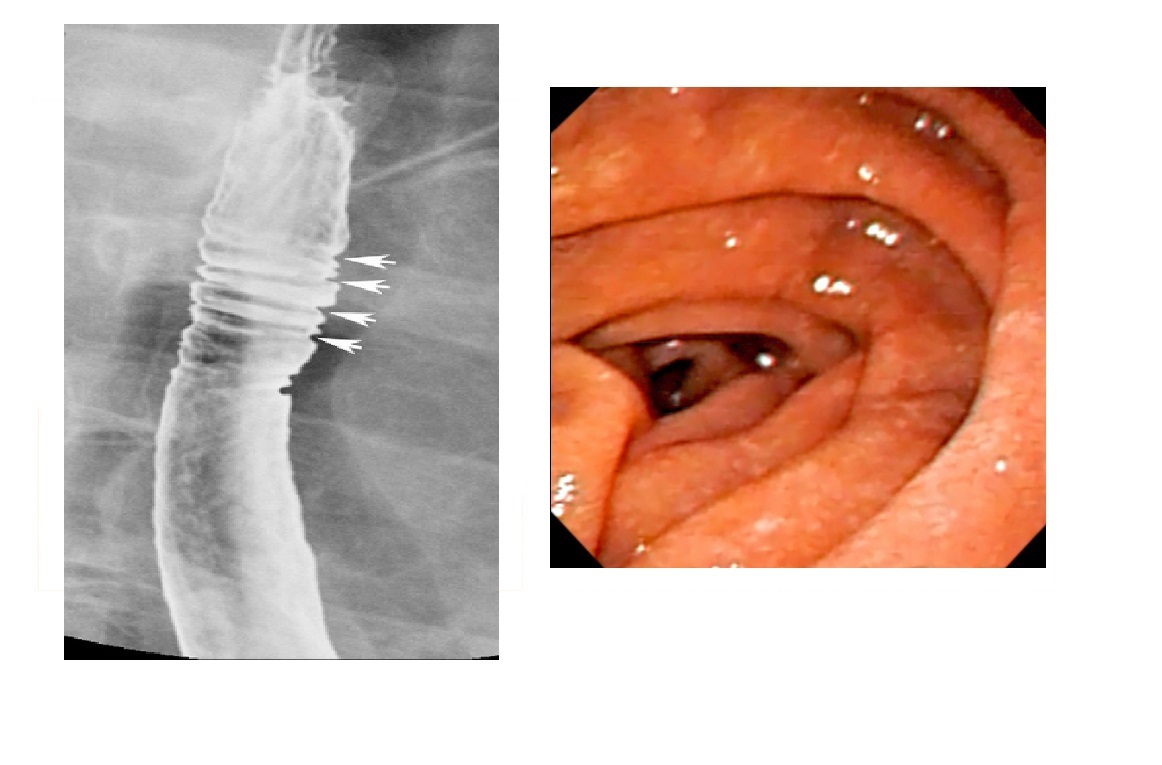

GIST

Well-circumscribed.

**Heterogenous, central necrosis is key **

Hypervascular

submucosal mass extending exophytically from GI tract

Stomach (60%) , dudoenum (30%) and oesophagus (10%)

Remember

- assocaited NF-1

- Carneys triad

- Pulmonary condromas, Exrtra-adrenal paragangliomas, GIST